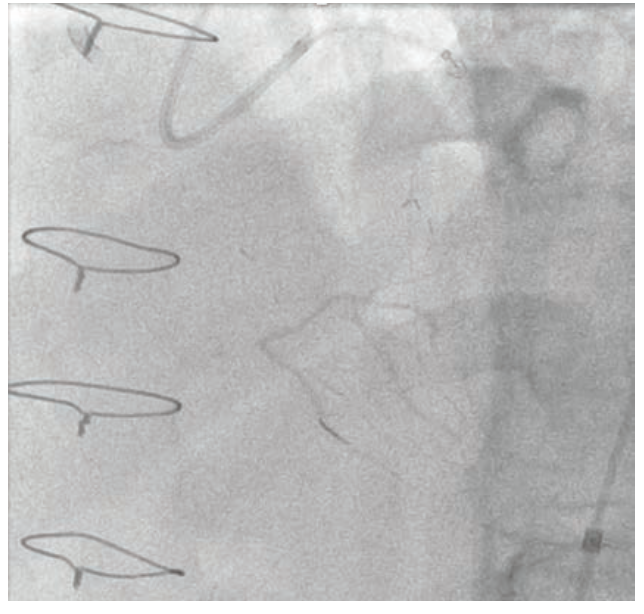

Dual access was achieved with a 7 French Amplatz Left (AL)-1 guide catheter and a 7 French Extra Backup (EBU) 3.75 guide catheter. Based on dual-injection angiography, the proximal cap was ambiguous due to a tortuous right ventricular (RV) marginal branch and the occlusion was long (>20 mm) (Figure 1). Therefore, we decided to attempt retrograde techniques first. After administering heparin to a goal activated clotting time (ACT) of >350, a workhorse wire was advanced through a low-profile microcatheter into the first septal perforator. The wire was exchanged for a specialty wire that was used to cross septal collaterals. We had difficulty advancing the microcatheter into the septal perforator, as it was jailed with a previously placed stent (Figure 2). Here, we used a 1.5 mm x 20 mm TAKERU balloon to dilate the stent struts. We were able to advance the microcatheter into the septal perforator and into the distal vessel (Figure 3). The connection was made with a reverse controlled antegrade and retrograde tracking (R-CART) technique (Figure 4). Overlapping drug-eluting stents were placed and aggressively post dilated. Final angiography demonstrated no residual stenosis, dissection, or perforation (Figure 5). The patient was placed on dual antiplatelet therapy for six months.